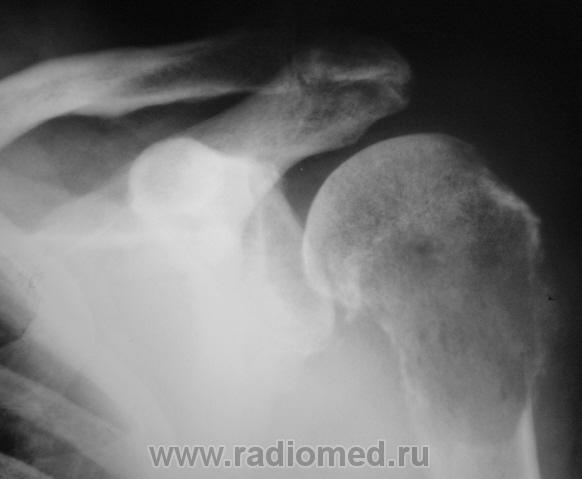

Нарушая все каноны обсуждения, но пользуясь тем, что Татьяна Валентиновна прокомментировала, хочу задать ей вопрос. Ваше мнение по поводу представленного ниже.

Хотела сразу написать "метастаз почечноклеточного рака". А если серьезно, Валентин Львович, подобная картина: литический очаг деструкции, со вздутием, разрушением коркового слоя, периостозом, требует морфологии, т.к. рентгеновская картина не специфична для какой-то определенной нозологии, диф. ряд включает и метастаз и первичную опухоль кости (прежде всего ходросаркома, остеосаркома, лимфома, ЗФГ).

Сам заключения не видел, но коллега терапевт информировал, что из областного ОД пришла гистология - "хондросаркома".